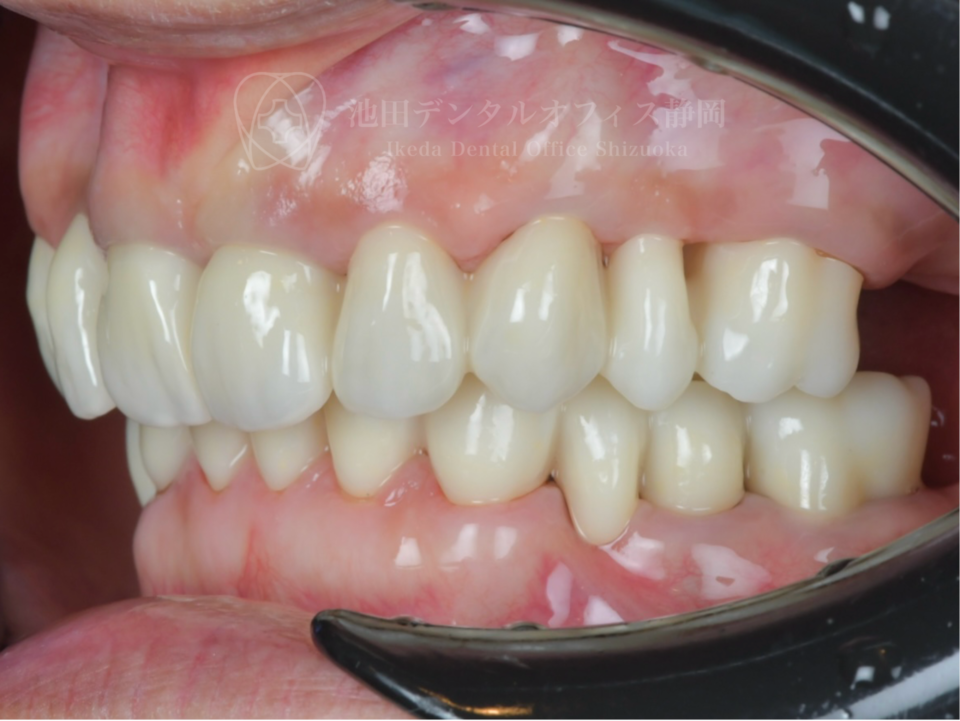

過去にいろんな歯医者で部分的な治療を受けた結果、噛み合わせがずれ様々な問題を抱えていた患者さんです。全体の治療を決意され、他県から新幹線を乗り継いで通院していただきました。